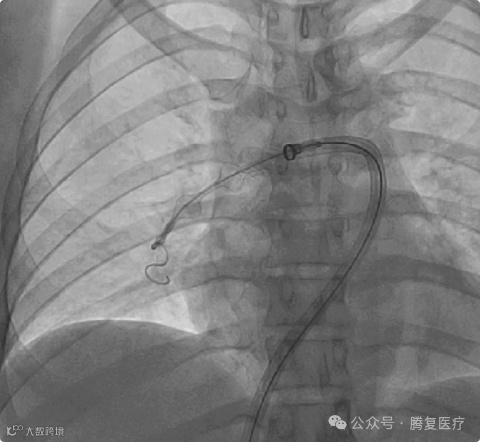

⾎栓由⽀架收集后进⼊抽吸导管内 ,并在负压抽吸状态下进⼊抽吸导管中。右肺动脉⾎栓清除后 ,同样方法清楚左侧肺动脉血栓

肺动脉血栓图